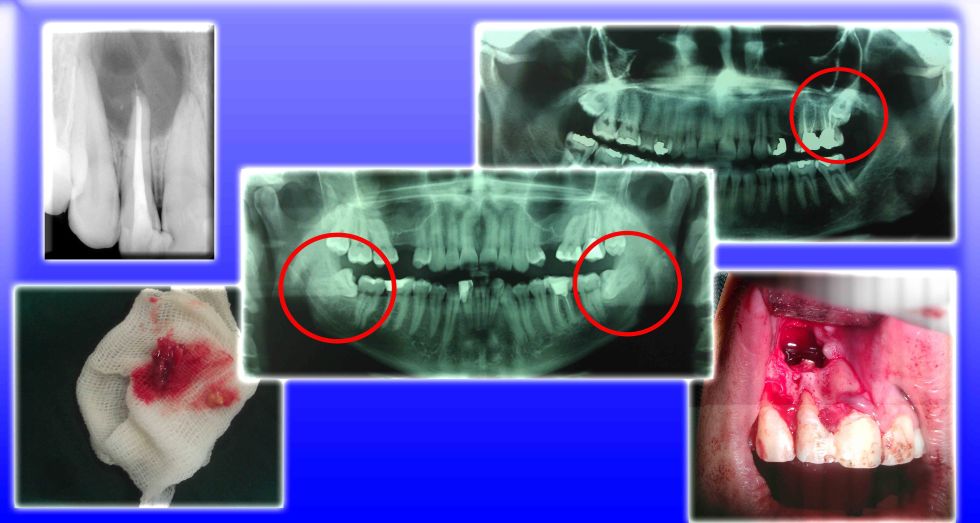

Dr. Mohammad Esmaeelinejad

DDS, OMFS

Assistant Professor, Department of Oral and Maxillofacial Surgery -

Dr. Farzad Aghdashi

DDS, OMFS

Assistant Professor of Oral & Maxillofacial Surgery, Shahid Beheshti University of Medical Sciences, Tehran, Iran